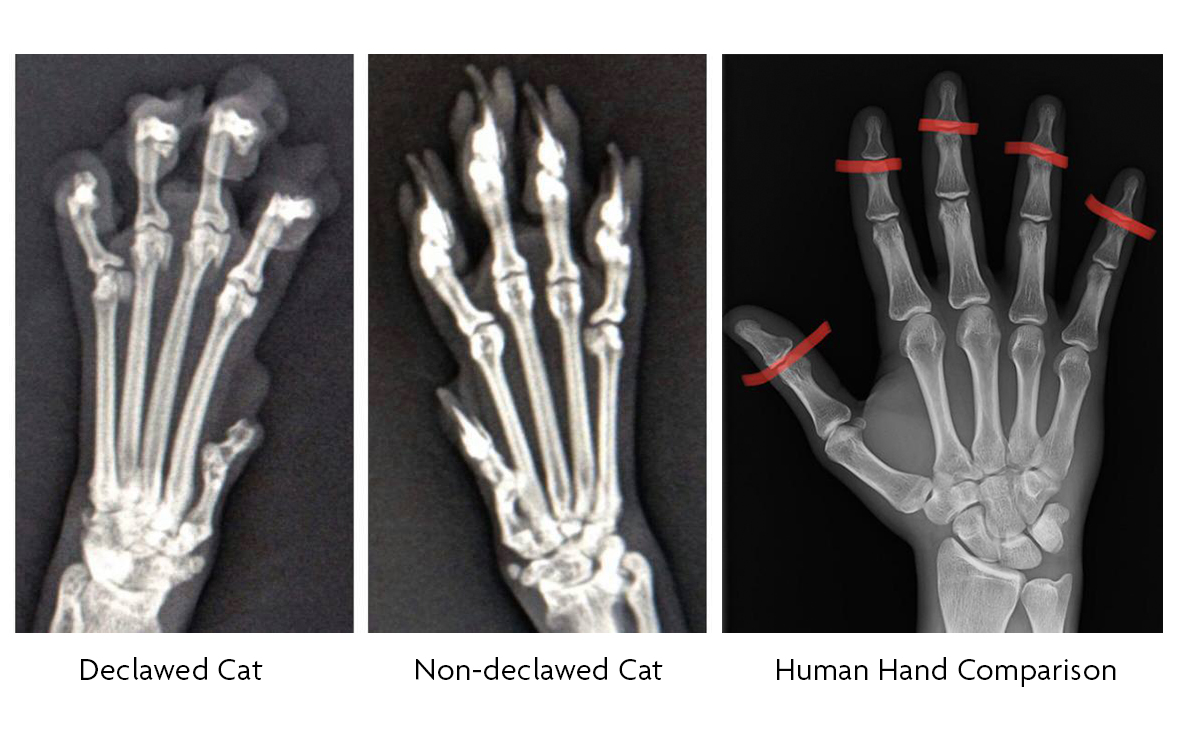

Declaw 12 copy